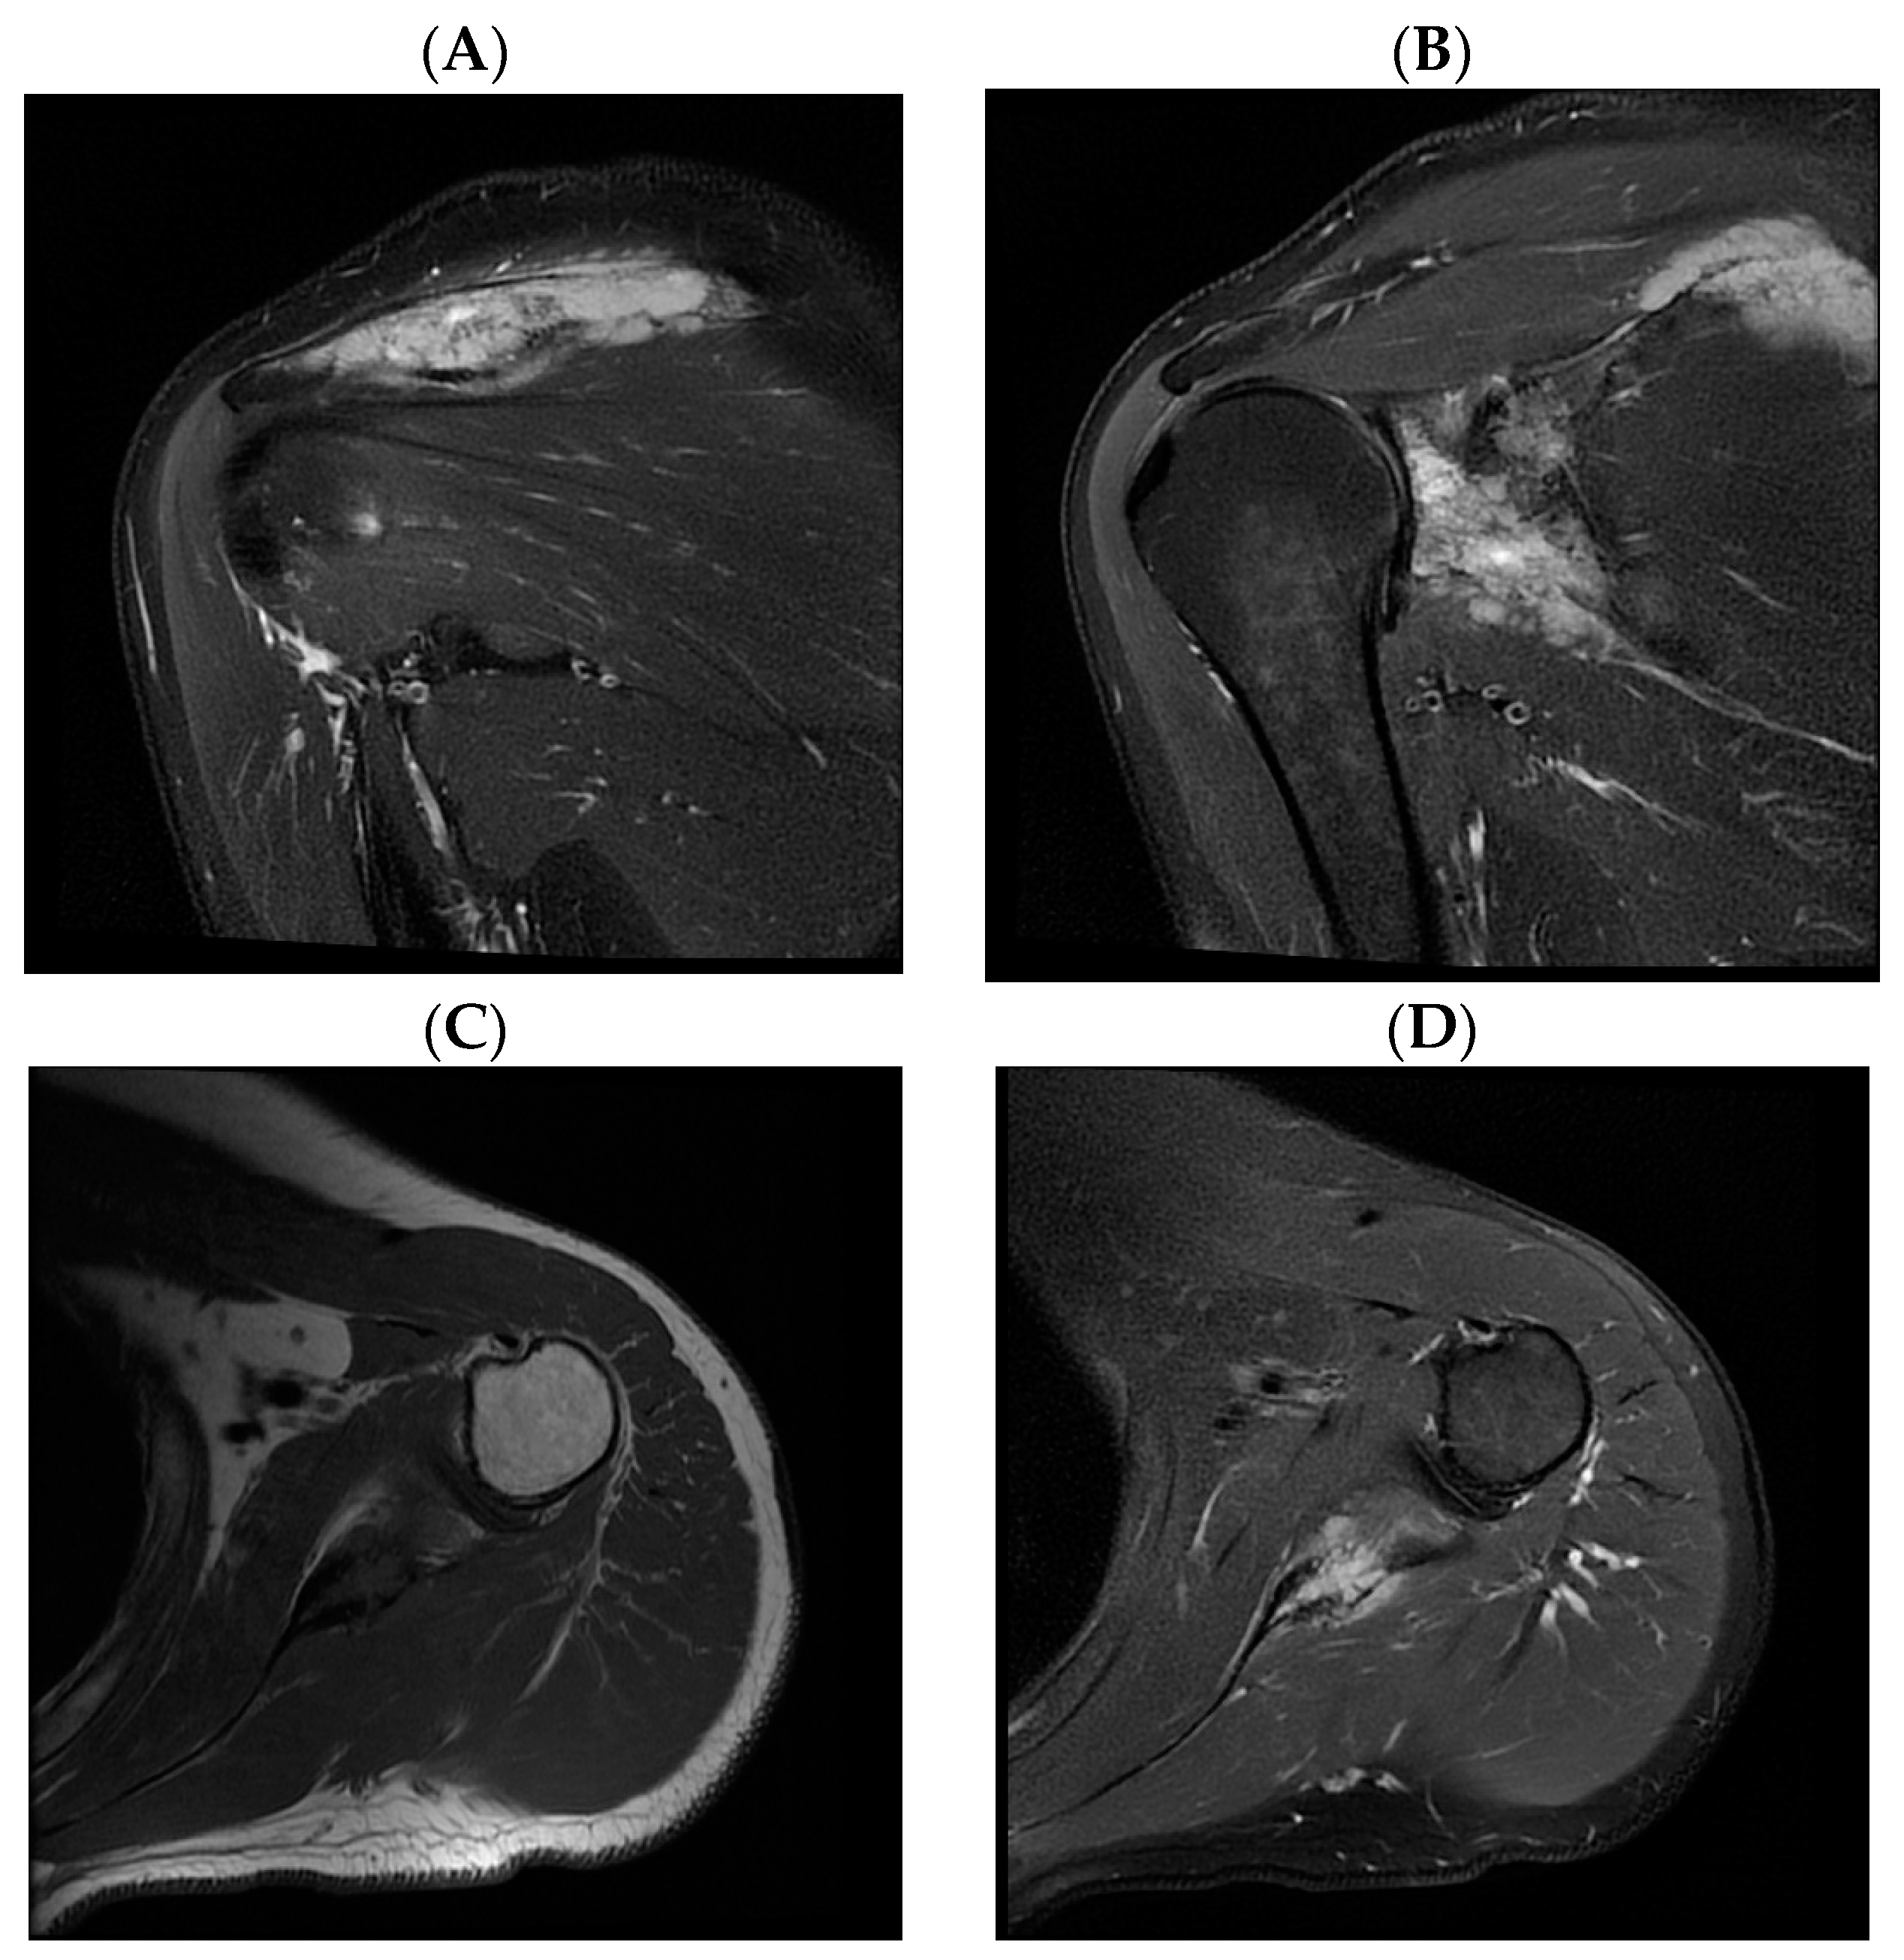

2. Case Report

| Our patient | M/45 y | Paresthesia, tingling, numbness and edema of the little and ring fingers | Two years/ two years | Surrounding soft tissue | R-CHOP chemotherapy + radiotherapy | Remission |